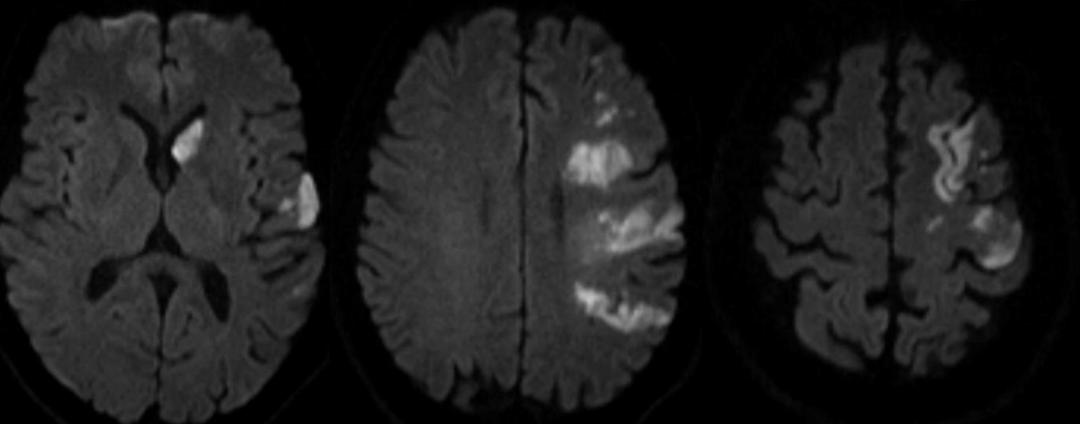

男39岁,因右侧肢体无力,言语障碍伴反应迟钝5小时。入院查体:嗜睡,言语障碍,反应迟钝,右侧肢体肌力1级,右侧病理增征阳性,入院后查心电图及心脏彩超未见异常,腰穿颅压200毫米H20,脑脊液常规生化未见异常。头颅DSA示左侧颈总动脉及左侧锁骨下动脉闭塞。

答案:血管型梅毒。青年脑卒中的发病率为(48~240)/10万。国内报道的青年脑卒中占所有卒中的13.44%。其常见原因有:早发性动脉粥样硬化、心源性栓塞、血液成分异常、烟雾病、炎性动脉病等。炎性动脉病主要包括大动脉炎、变态反应性疾病和特异性感染(如梅毒、带状疱疹、疟疾、钩端螺旋体)、非特异性感染(如系统性红斑狼疮)。本病例给的信息不足以诊断梅毒,目的是提醒老师们血管病的病因不要忘记梅毒。

男性50岁,下午睡觉后家属喊不醒,大概4-5小时,之后反应淡漠,右下肢软瘫。

答案:神经梅毒。患者中年男性,急性起病,主要表现为反应迟钝,右下肢软瘫,头颅影像提示以双侧顶枕叶对称性高信号,左侧丘脑点状病灶,额颞叶萎缩。老师们想到了低血糖脑病、PRES、脑梗死、CO中毒等。小僧悟道老师一眼就看出来是梅毒,着实厉害。与年龄不相符的脑萎缩是重要特征。